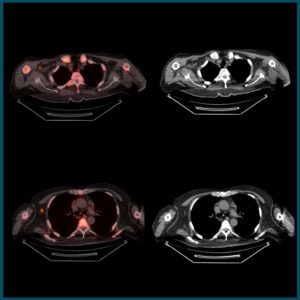

Advancing your expertise in PET-CT imaging to enhance cancer diagnosis and improve patient care.

Since its establishment in 2017, the Christie PET-CT Academy has been a leading centre of excellence for advancing education and training of professionals across the full spectrum of PET-CT diagnostic services. Part of The Christie NHS Foundation Trust the PET-CT Academy operates in partnership with Alliance Medical as part of the National Contract 1 (NC1) Molecular Imaging Collaborative Network (MICN), to provide a skilled workforce to meet ever-increasing patient needs across England, by equipping professionals to enhance diagnostic capabilities and work toward closing the gap in cancer survivorship.